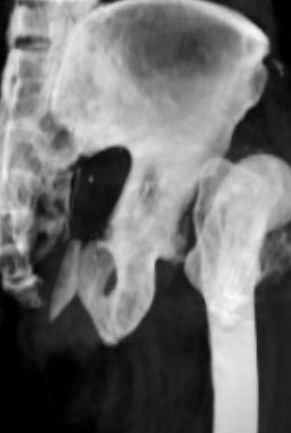

Уважаемые коллеги, Мужчина 1952 г.р. поступил в 36 больницу Екатеринбурга 1 июня 2004 г. Диагноз: Множественный перелом ребер слева, субтотальный гемоторакс, оскольчатый перелом шейки правого бедра. Повреждение таза не диагностировано.

17 июня 2004 г. - открытый остеосинтеза шейки бедра винтами с костной аутопластикой. Заживление раны первичное. Выписан 1 июля. 4 июля отметил укорочение конечности. При контрольном осмотре через 1 месяц после остеосинтеза - передний вывих бедра. Неправильно срастающийся перелом костей таза. Вопрос - особенности эндопртезирования тазобедренного сустава в этой ситуации?